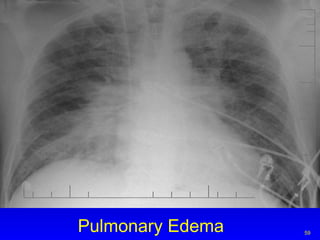

Pulmonary Edema

ARDS Congestion Interstitial and alveolar edema Collapsed or distended alveoli Bilateral

CARDIOMEGLY CONGESTIVE   HEART FAILURE Evolution of congestive heart failure and pulmonary edema. With Progressive Lt. Ventricular failure blood backs into the left atrium—then to the pulmonary veins (PULMONARY VENOUS HYPERTENSION) then to the pulmonary interstitium (INTERSTITIAL EDEMA) then to the alveoli (ALVEOLAR EDEMA)

Congestive Heart Failure Increased heart size:  cardiothoracic ratio  >0.5 Large hila with indistinct markings Fluid in interlobar fissures Pleural effusions, alveolar edema